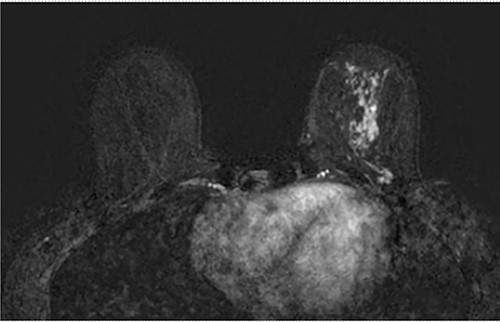

Clinical findings during follow-up were unremarkable until 2020, when she represented with a new lump in the reconstructed left breast neighbouring the mastectomy scar inferiorly. A 1 cm subcutaneous lump with no skin tethering, was palpable along the uniting suture line of the ADM-pectoral muscle. Imaging with ultrasound was indeterminate. This implant proximity rendered it unsuitable for core biopsy due to the high risk of iatrogenic implant perforation (Fig. 2). Subsequent MRI (Fig. 3) illustrated an 11 mm low signal lesion correlating clinically to the palpable lump with mild enhancement but indeterminate appearance.

Axial post contrast fat-saturated sequence identified bilateral implants and an 11 mm oval foci of type 1 enhancement in the site of clinical concern on the capsule (black arrow).